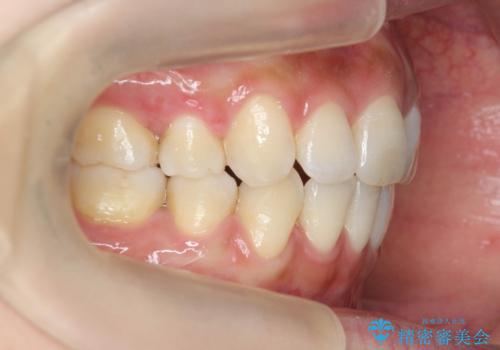

ガタつきと口元の改善 抜歯を伴うワイヤー矯正

- 唇の閉じづらさと、前歯のがたつきの改善を希望され来院されました。

抜歯を行わなくてもなんとか並べられる歯並びですが、唇の閉じづらさをしっかりと改善するため抜歯を伴うマルチブラケット矯正を行うこととしました。

前歯をしっかりと後方に引いたことで、唇は閉じやすくなり、仕上がりに満足いただくことができました。